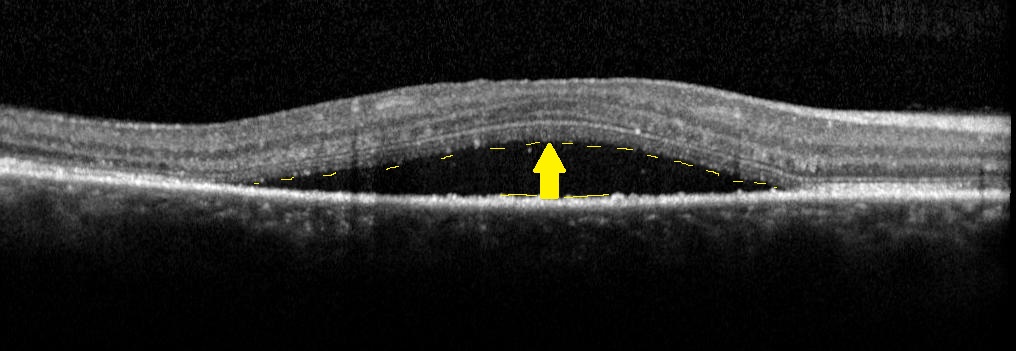

La CRSC est une pathologie de la choroïde, tissu de soutien très vascularisé de la rétine, qui se traduit par la survenue de bulles de liquide sous la rétine alimentées par des points de fuite au niveau de l’épithélium pigmenté de la rétine.

Il s’agit d’une pathologie le plus souvent aiguë. Dans sa forme chronique, elle est appelée épithéliopathie rétinienne diffuse. Le diagnostic est confirmé par l’OCT et l’angiographie à la fluorescéine souvent complétée par l’angiographie au vert d’indocyanine.